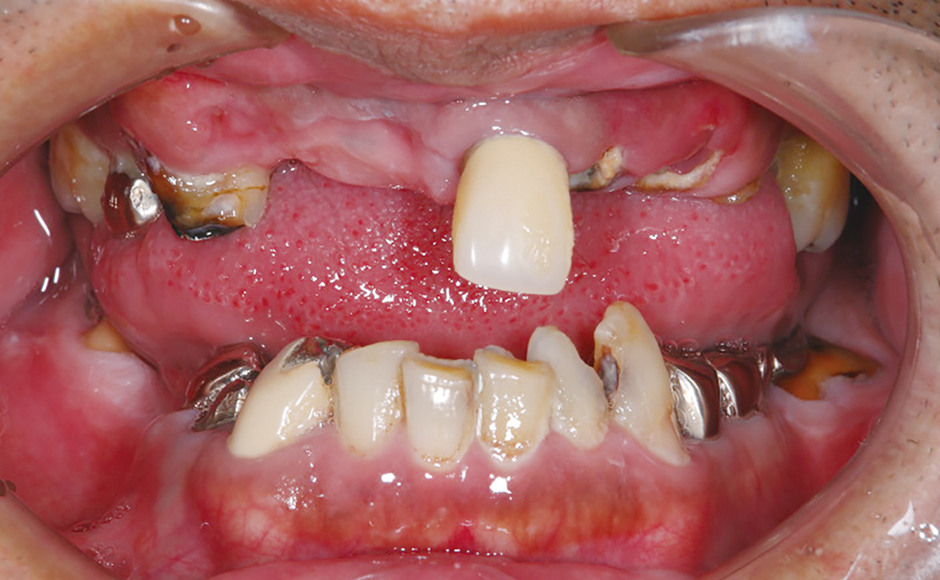

症例1:患者の主訴を考慮し、抜歯即時埋入・即時プロビジョナライゼーションを計画